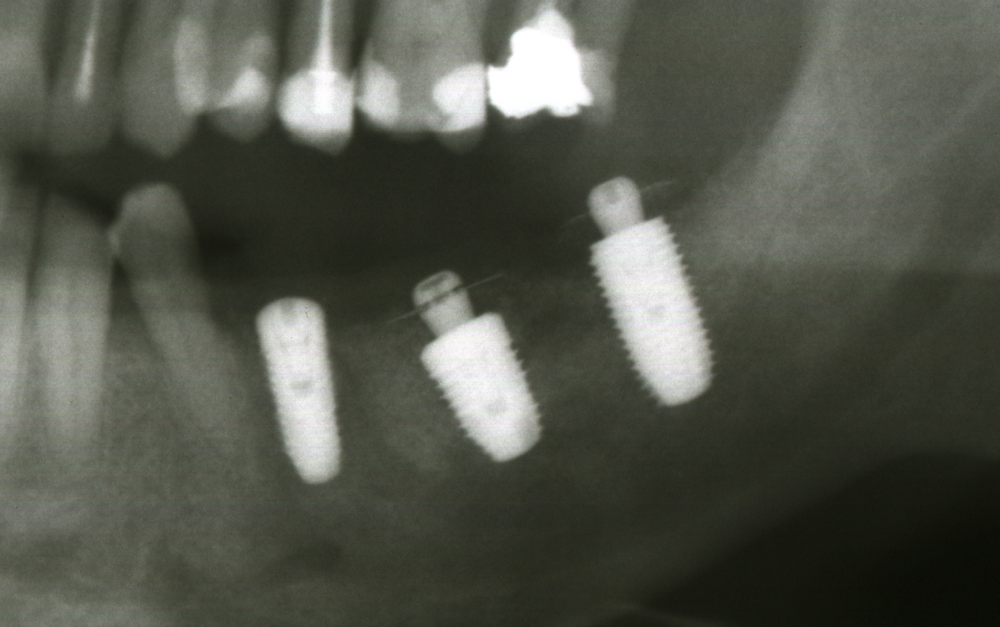

Титановите мембрани са твърди, ригидни приспособления, които се поставят в участъци с необходимост от увеличаване на костния обем - най-вече в областта на имплантологията, но също при радикуларни кисти и много рядко след екстракция на ретинирани мъдреци, при дефкетни фрактури, пострезекционни дефекти на челюстите, тежки остеомиелити и специфични възпаления на костта. Идеята на титановата мембрана е да предпази меките тъкани от колапс, поне за известен период от време, през който период под мембраната да започне костообразуване. През първите шест - осем месеца титановата мембрана оказва своя ефект, след което вече е безсмислено да остава в устата на пациента.

Tent screw - винтове за

фиксиране на титановата мрежа